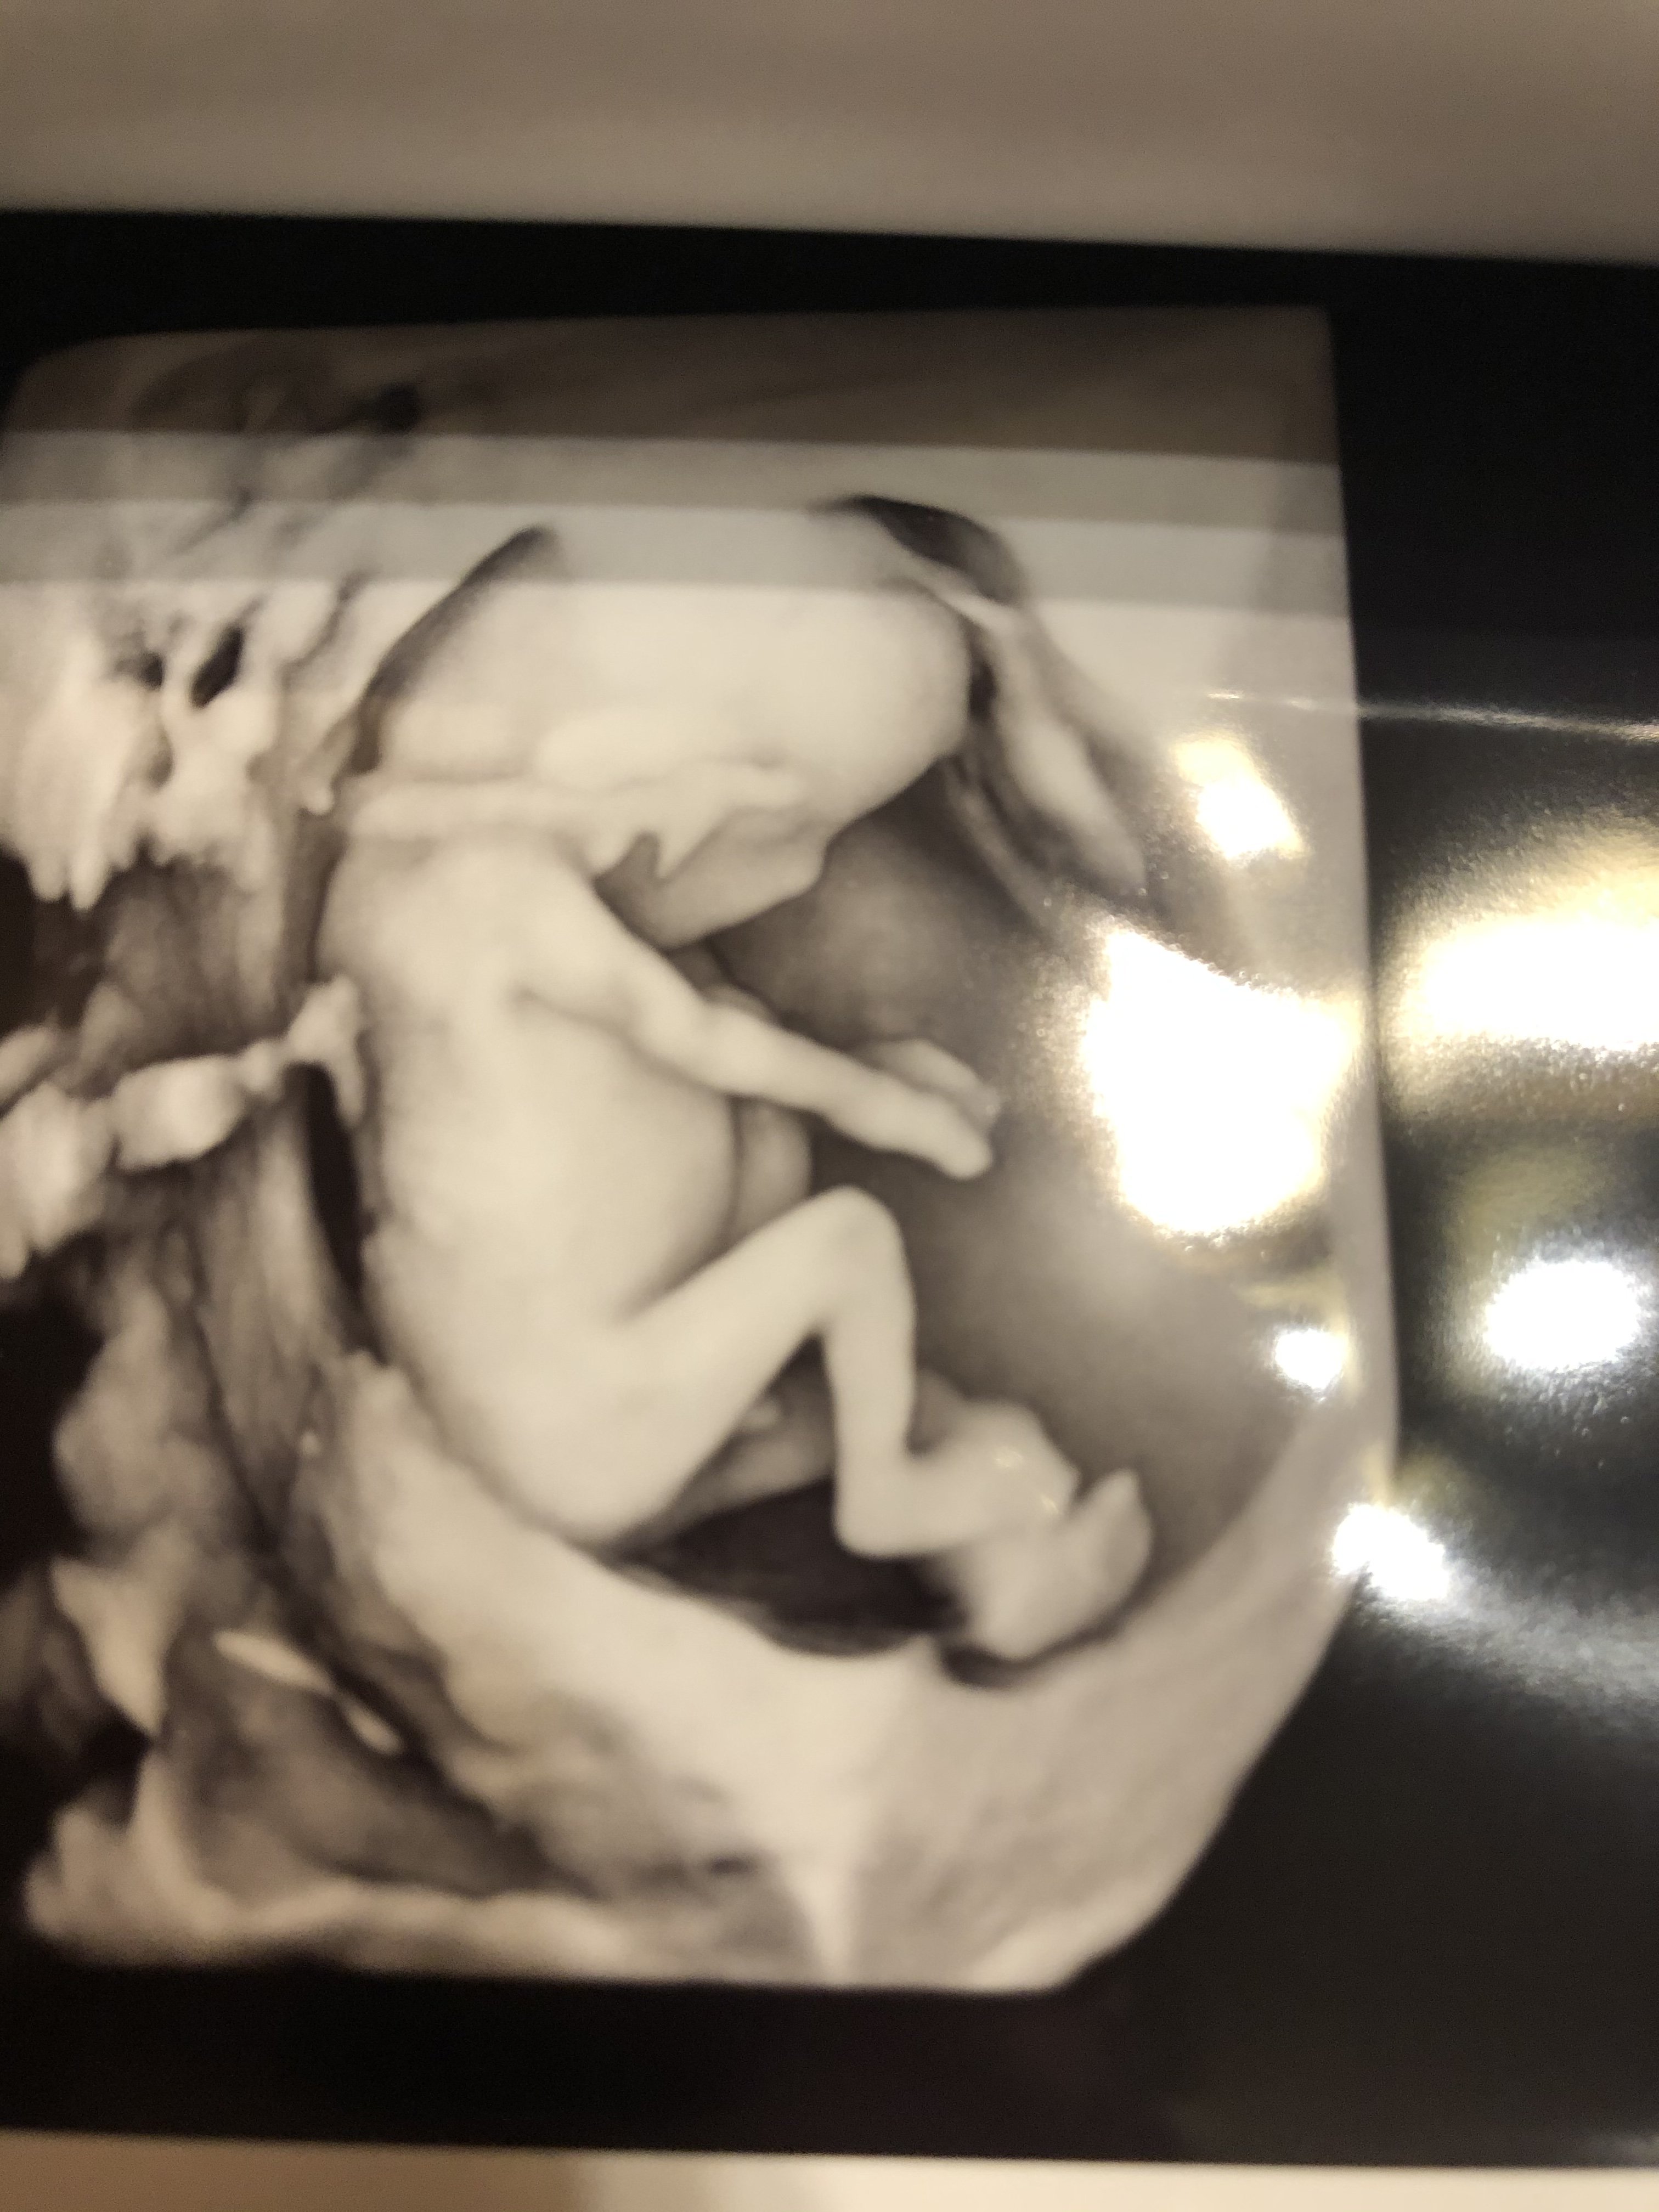

Jestem po!

Maglowal mnie z góry. Z dołu na zmianę haha dziecko się tak ruszało ze szok! (Jednak to nie jelita hehe 🤭) potwierdziły się moje czujki ze to ruchy..

Ręce

Nogi

Wszystko jak trzeba na miejscu 🥰

Termin 07.04! Dziecię ma 7cm

Także według OM i USG tak samo wszyatko cacy się pokrywa...

chyba o płci nie muszę się wypowiadać 🙈🙈🙈🙈🙈🙈 jednym słowem - chińskie kalendarze kłamią!!

Załączniki

• 09CDEE4A-39E9-443B-8296-D0962E2D6F40.jpeg

09CDEE4A-39E9-443B-8296-D0962E2D6F40.jpeg

1 MB · Wyświetleń: 168